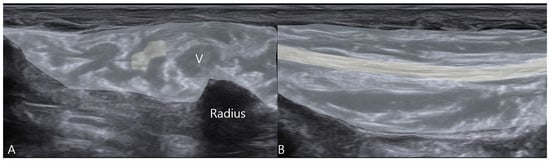

2.4. Therapeutic Intervention

- Mechanical Neurolysis: The injected fluid creates a physical separation between the nerve and the surrounding constrictive tissues, lysing adhesions and effectively expanding the perineural space. This immediately alleviates mechanical compression and restores normal nerve gliding, as evidenced by the resolution of snapping on follow-up ultrasound.